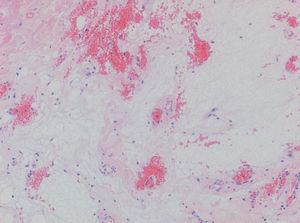

Se realizó extirpación de la lesión. En la histología se observó, en la dermis y extendiéndose a tejido celular subcutáneo, una lesión multilobulada y con márgenes mal definidos. Esta tumoración contenía una prominente estroma mixoide en el que se encontraban vasos de paredes finas y escasa celularidad. No se apreciaban atipias ni mitosis. La estroma mixoide se teñía fuertemente con la técnica de hierro coloidal (figs. 2 y 3). Ante el diagnóstico de angiomixoma superficial se realizó una ecocardiografía en la que no se detectaron mixomas auriculares. En la exploración física no se observaron otras tumoraciones ni lesiones pigmentadas que pudieran hacer sospechar un síndrome asociado. Tras 6 meses de seguimiento no se han observado signos de recurrencia.

Fig. 2.--Se observa una tumoración situada principalmente en la dermis compuesta por una prominente estroma de aspecto mixoide, con escasa celularidad y proliferaciones vasculares de paredes finas. Se observa un discreto infiltrado inflamatorio alrededor de los vasos.